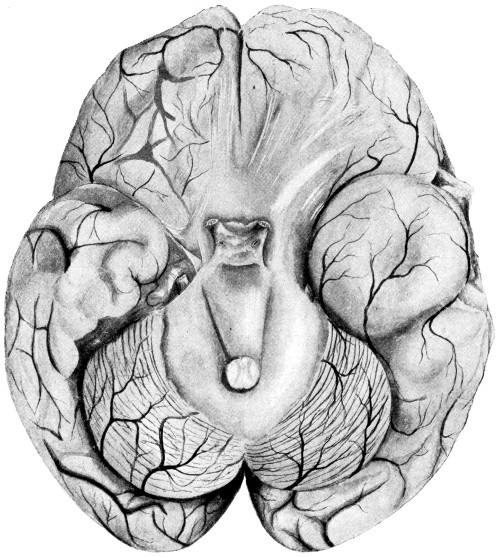

Fig. 1. Cranio-cerebral Topography. 1, The nasion; 2, The inion; 3, The mid-point between nasion and inion; 4, The Rolandic fissure; 5, The superior temporal crest; 6, The inferior temporal crest; 7, The Sylvian point; 8, The anterior horizontal limb of the Sylvian fissure; 9, The vertical limb of the Sylvian fissure; 10, The posterior horizontal limb of the Sylvian fissure; 11, The parietal prominence; 12, The malar tubercle; 13, The lambda; 14, The first temporo-sphenoidal sulcus; 15, The external parieto-occipital sulcus; 16, The lateral sinus; 17, 17, 17, The level of the base of the cerebrum; 18, The external auditory meatus; 19, 19, Reid’s base-line. (Reproduced, by the permission of Mr. H. K. Lewis, from the author’s work on ‘Landmarks and Surface-markings’.)

Larger illustration (top)

Larger illustration (bottom)